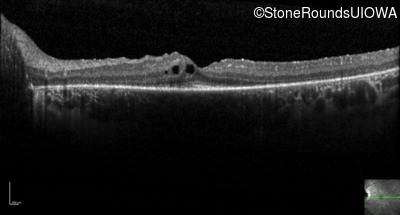

Optical Coherence Tomography - Right -

20/20 -1

Exemplar / OCT Stack